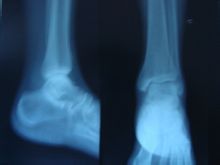

扭伤在校园中经常发生,对于打篮球,踢足球的男同学来说,脚踝关节是最容易扭伤的部位,一旦扭到,最直接的反应就是痛,然后才会依扭伤的程度,看看是否会有肿胀或是瘀血的情形。对于这种伤害,许多同学不以为意,而常常旧疾未愈,新伤复发,成为习惯性反复扭伤,影响运动机能与日常生活学习。

踝关节扭伤后,局部软组织因暴力损伤而出血或渗血,使踝部肿胀疼痛,活动后症状会加重。如果此时按揉或热敷伤处,不但不能使血肿消退,反而会人为地加重患部的损伤,致使伤处血管扩张,增加出血量,使伤情进一步恶化。有的病人踝关节扭伤后局部伤痛并不是十分明显,但盲目热敷处理或草率地揉捏按摩反而会加重踝部伤痛